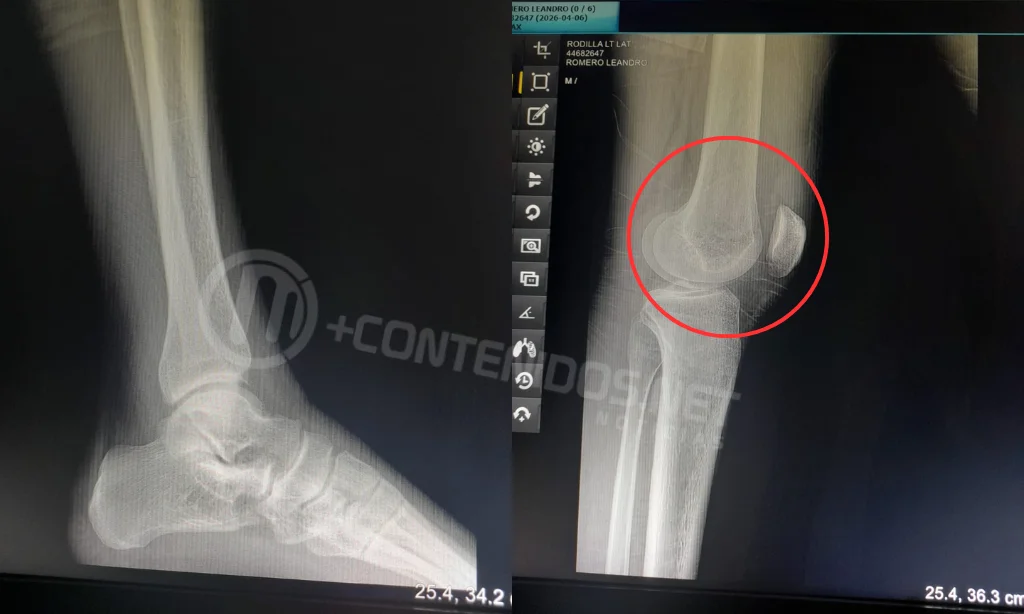

Tras radicar la denuncia, solicitó ser examinado por el médico policial debido a las múltiples lesiones sufridas. Asimismo, señaló que el comercio cuenta con cámaras de seguridad, aunque desconoce si estaban en funcionamiento al momento del hecho.

La causa quedó en manos de la Justicia, y el denunciante manifestó su intención de avanzar penalmente contra los presuntos agresores por las lesiones sufridas.